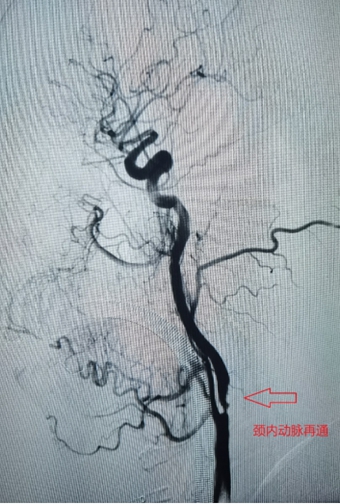

1、左侧颈内动脉末端闭塞,急诊导管抽栓+支架拉栓1例;